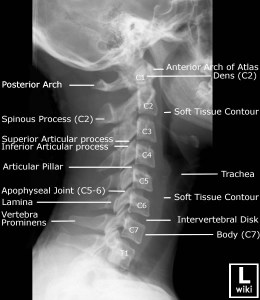

Image source from WikiRadiography (Wetpaint) here. Read about cervical ribs and thoracic outlet syndrome here.